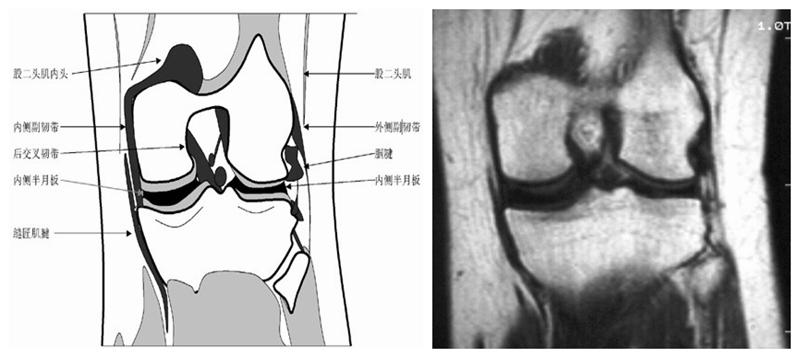

膝关节冠状面MRI解剖

显示内外侧副韧带、腘肌和拱状韧带,有无信号和结构改变,侧重关节胫股软骨的两边和半月板的体部。

冠状位解剖第三层